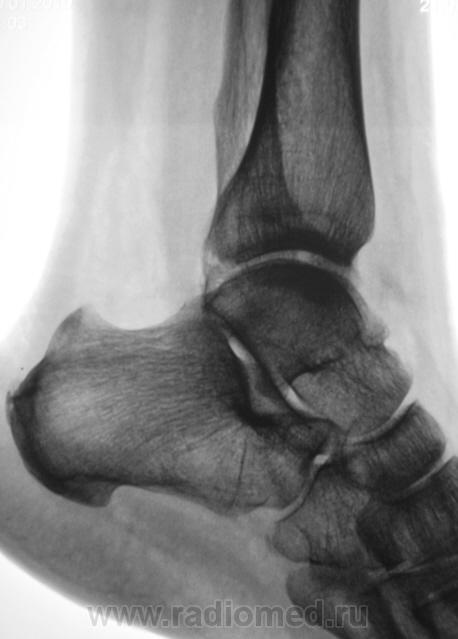

А, может быть, с учетом деформации малоберцовой кости, на боковой рентгенограмме, можно предположить, что, "это", откол фрагмента костной ткани от дистального эпифиза б/берцовой кости.

Если говорить о травме ( нужно учесть механизм), то можно предположить вдавленный перелом с огранич., но интенс. действием травмирующей силы с компрессией ( уплотнением) костной ткани.